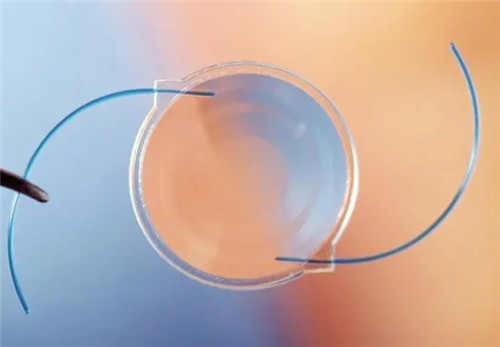

三焦点晶体:相比传统单焦点,可同时优化远、中、近视力,术后不用戴老花镜。

设备靠前,术前检查超全(OCT、角膜地形图等)。

严格术前评估:确保患者符合手术条件,降低术后眩光等风险。